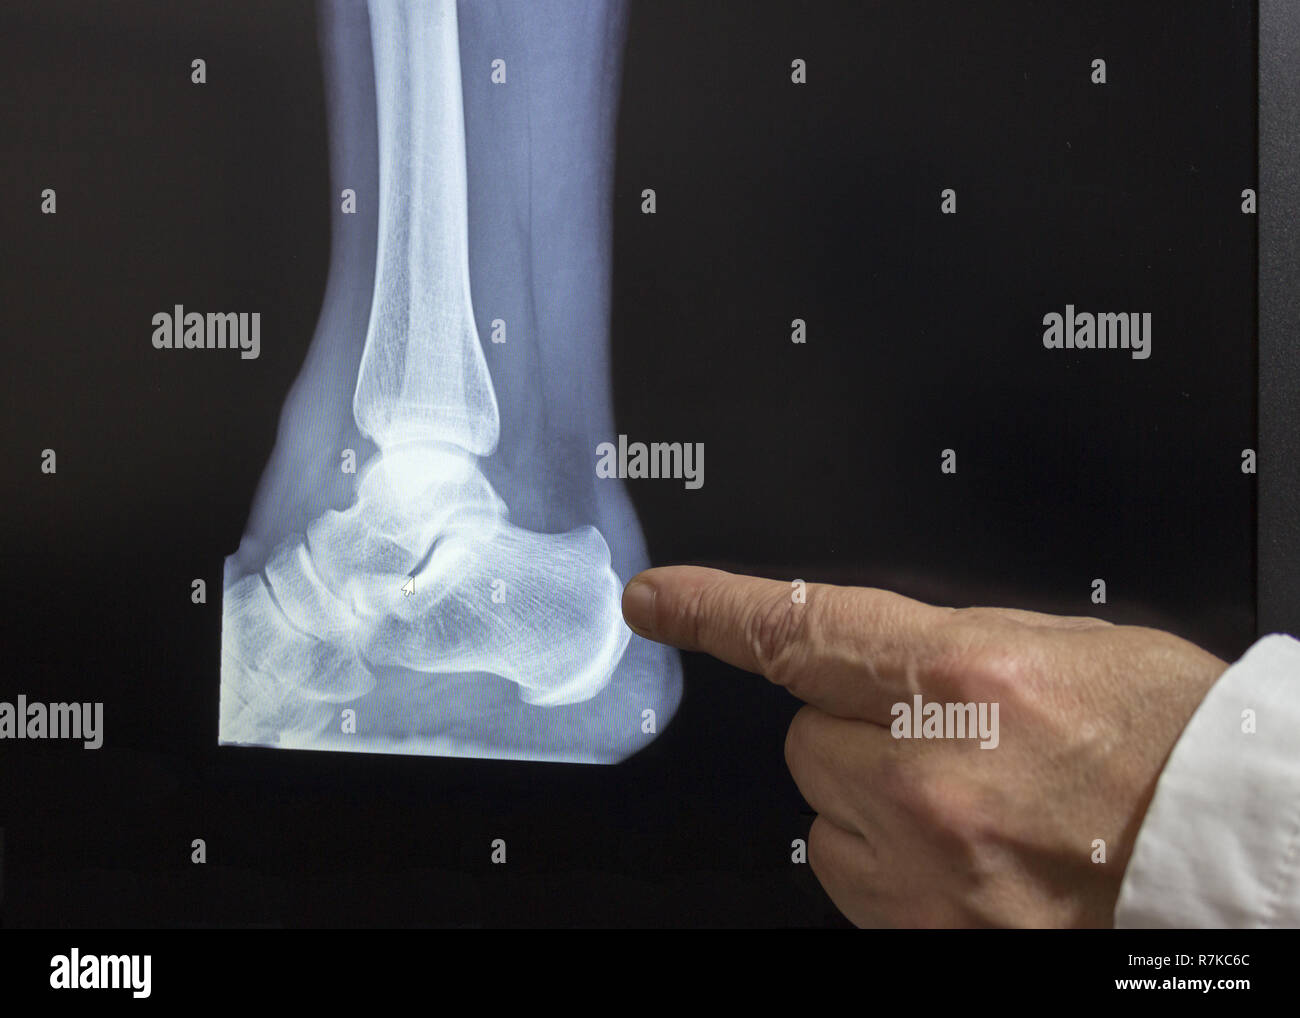

Rx Fractura En Talon . Web las fracturas calcáneas producen diferentes señales y síntomas, dependiendo de si son fracturas traumáticas o por sobrecarga. Web cuando el calcáneo está fracturado, el talón está dolorido y, por lo general, el pie y el tobillo están hinchados y no soportan el.

Ángulos de gissane (blanco) y böhler (negro). Web los síntomas de una fractura de talón incluyen dolor, hinchazón y moretones en el talón. Web las fracturas del calcáneo (hueso del talón) se suelen producir como resultado de una gran fuerza.

Rx Fractura En Talon - Ángulos de gissane (blanco) y böhler (negro). Web cuando el calcáneo está fracturado, el talón está dolorido y, por lo general, el pie y el tobillo están hinchados y no soportan el. El diagnóstico se realiza mediante radiografía y, de. Web las fracturas del calcáneo (hueso del talón) se suelen producir como resultado de una gran fuerza. Web los síntomas.

Rx Fractura En Talon - Web las fracturas calcáneas producen diferentes señales y síntomas, dependiendo de si son fracturas traumáticas o por sobrecarga. Web cuando el calcáneo está fracturado, el talón está dolorido y, por lo general, el pie y el tobillo están hinchados y no soportan el. Web las fracturas del calcáneo (hueso del talón) se suelen producir como resultado de una gran fuerza..